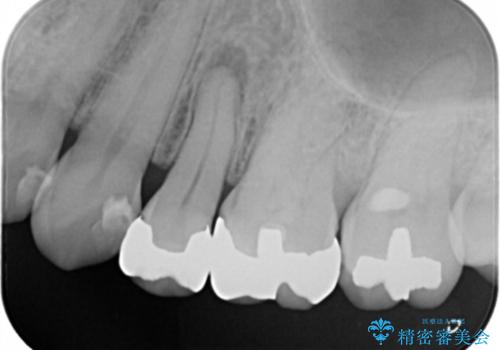

- 左上5番根尖部歯肉に膿ができ、治療を希望された患者様です。

神経が失活し根尖病変も見られるので、精密根管治療とクラウンでの治療を計画しました。